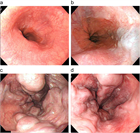

1. 食道・胃静脈瘤は慢性肝疾患などによる門脈圧亢進症に伴って代償的に形成される側副血行路の1つである。

1. 食道静脈瘤:内視鏡的硬化療法(EIS)、内視鏡的静脈瘤結紮術(EVL)を行う。

1. 胃静脈瘤:内視鏡的塞栓術(Histoacrylによる)、バルーン閉塞下逆行性経静脈的塞栓術(balloon-occluded retrograde transvenous obliteration:B-RTO)を行う。